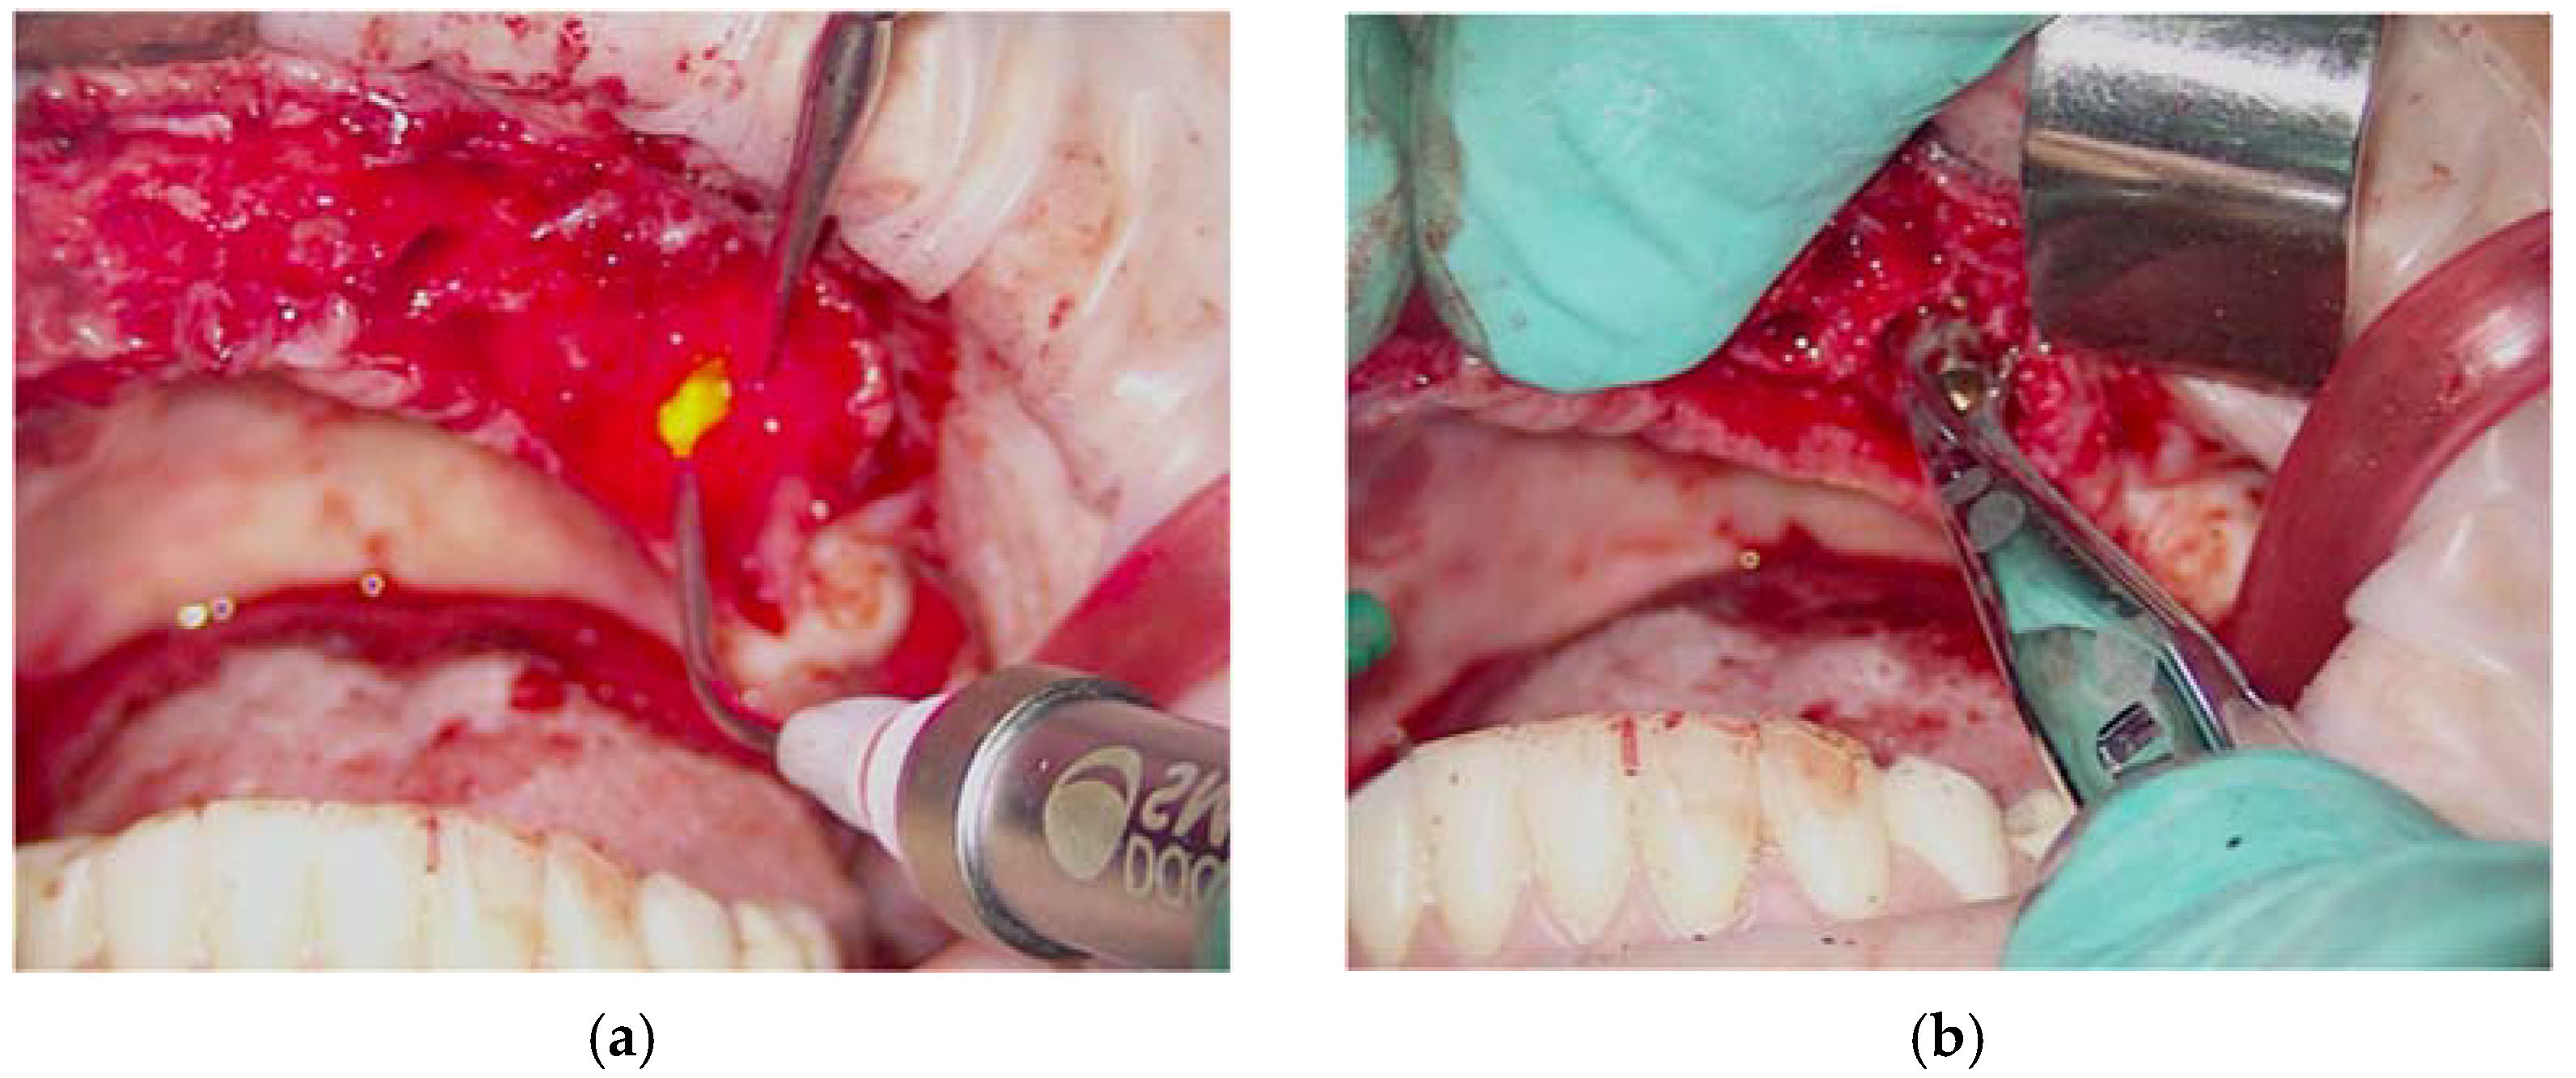

Surgical Procedure